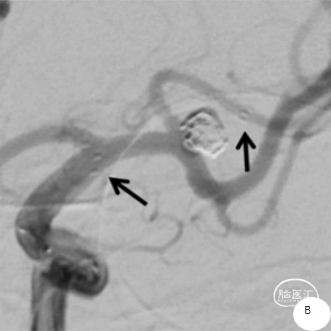

患者推入放射科导管室平躺于检查床上,常规心电、血压监护;消毒右侧腹股沟区,铺手术巾,气管插管全身麻醉后,穿刺右侧股动脉,置入导管鞘,成功后置入超滑导丝及椎动脉导管,行左侧颈内动脉3D造影术,明确动脉瘤栓塞和辅助支架置入的工作体位。

载瘤动脉细小,经测量为0.87mm,角度为反向角度,释放支架易贴壁不良,颈内动脉段血管入路较迂曲,需要支撑力及柔顺性较好的微导管,同时避免微导管拉直血管并使血管位移而影响定位。

引入8F 导引导管及6F 中间导管至左侧颈内动脉,接加压管肝素盐水(500ml盐水2000单位肝素)4路;200cm Synchro-14微导丝配合SL-10微导管超选进入左侧大脑中动脉M1段上干备用(大脑中动脉M1段上干与动脉瘤瘤颈关系密切);200cm Synchro-14 微导丝配合Echelon-10微导管超选进入瘤体内,沿微导管填入Target 3mm×10cm 3D弹簧圈一枚成篮良好;后经SL-10微导管送入Atlas 3.0mm×24mm支架直至支架中部位于瘤颈处,缓慢释放支架,释放支架时通过半释放状态在瘤颈部小心推压将支架形成“穹窿”,穹顶部分支架可疝入瘤颈处,将宽颈动脉瘤变为窄颈。造影示支架稳定、帖壁良好;继续沿微导管行动脉瘤内弹簧圈栓塞术,先后放入2mm×6cm(两枚)、2mm×4cm、2mm×4cm、1.5mm×2cm弹簧圈共6枚;

释放支架前经导引导管缓慢注入替罗非班6ml,之后持续静脉泵入,速度5ml/h。手术历时60分钟,麻醉顺利苏醒,神经系统查体:未见阳性体征。NIHSS评分:0分;Raymond分级:Ⅰ级,mRS评分:0分。术后即刻行C-arm CT头颅扫描,未见出血,动脉瘤填塞致密,支架开放良好。

术后6个月复查造影示:弹簧圈致密充填瘤体内,瘤体消失,左侧颈内动脉及大脑前、中动脉均显影良好,载瘤动脉通畅,形态和血管直径较动脉瘤栓塞前无明确变化。支架形态良好,未见移位及血栓形成。